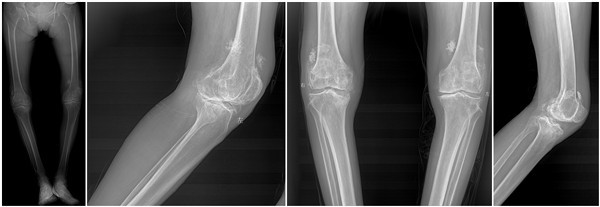

65岁郭女士10年前开始双膝关节疼痛,病情反复,半年前双膝关节疼痛加重,持续性疼痛,休息后无缓解,行走约100m左右即感疼痛难忍,不能继续行走,患者十分痛苦,生活不能自理。近日以“双膝关节疼痛10年余,加重并活动受限半年”主诉来骨一科就诊入院。经入院查体:双膝关节屈曲内翻畸形,膝内侧压痛明显,髌骨摩擦试验阳性,浮髌试验阴性,双膝关节屈伸活动受限,左侧屈曲挛缩15°,内翻25°;右侧屈曲挛缩20°内翻30°。诊断为:双膝关节骨关节炎,拟行“双膝关节置换术”。

6月5日,由王坤正教授主刀,在宋金辉、王伟副教授及杨佩副教授的配合下,顺利完成首例PSI(patient-specific instrumentation, 病人个体化截骨导航模板)引导下双侧膝关节同期置换的手术。手术顺利实施,术后病人病情稳定,术后24小时双侧膝关节出血引流量明显较常规手术减少,右侧显性引流20ml,左侧30ml。病人术后疼痛明显缓解。